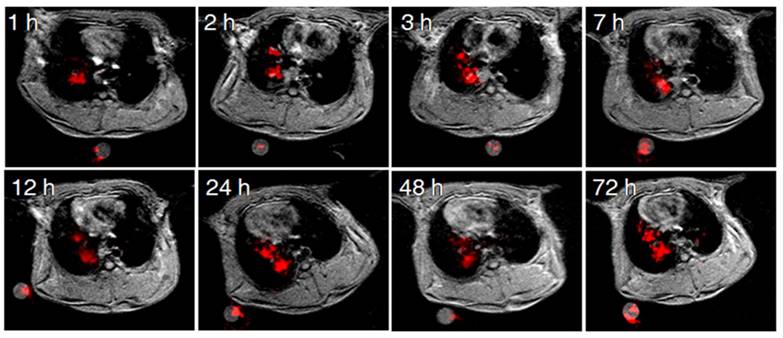

Pulmonary 19F imaging of the tumor with the M-PFC NP using the same IT delivery protocol mirrored the marked 1H R1mapping results closely. 19F signal was visually prominent in the Vx2 tumor at 1 h and this strong signal persisted over 72 h, as shown in Figure 3. 19F imaging with paramagnetic PFC nanoparticles is inherently less sensitive than 1H imaging due to the relative paucity of fluorine atoms per voxel and lower NMR sensitivity of 0.83. However, the magnitude of the 19F signal can be enhanced when gadolinium-lipid chelates, such as Gd-DTPA-BOA, that position the metal very close to the PFC core are included in the lipid surfactant [22, 31-33]. In the present study the low level of Gd-DTPA-PE placed the metal further away from the PFC molecules into the surrounding water, providing minimal benefit to the 19F signal.

Figure 3

Dynamic monitoring of 19F-MR enhancement at different time points post IT delivery of the M-PFC NPs. Image slices were acquired at different time points and examples selected to depict similar cardiothoracic regions.

In the present study, the high biocompatibility, ideal size, oxygen dissolving capacity and natural bioelimination via exhalation contributed to the success of M-PFC NP in the Vx2 rabbit lung tumor model. As evidenced by 1H and 19F MR imaging, the IT M-PFC NP penetrated into the growing Vx2 tumor, slowly and progressively over 12 h and persisted for 72 h. The magnitude and persistence of M-PFC NP via intratracheal delivery into the tumor was dramatically better than the minimal and transient MR T1 signal response noted at 2 h following IV injection. Moreover, IT M-PFC NP were essentially confined to the cancer, lung and airways, whereas, the biodistribution of IV M-PFC NP extended beyond with systemic accumulation in the liver and spleen.

Extravascular distribution of nanoparticles into tumors following intravenous injection remains a significant barrier to the clinical translation of nanotechnology [49]. Although some particles are capable of penetrating beyond the circulation and into the tumor, inhomogeneous distribution within the lesion with large portions of the cancer unaffected is common [50]. Intratumoral delivery by IT M-PFC NP had very homogeneous distribution, excluding only the necrotic regions. In each animal, the IT fluorescent M-PFC NP densely coated the tumor cells and their microenvironment, which was evidenced by the strong T1 shortening and prominent 19F signals measured with MRI.